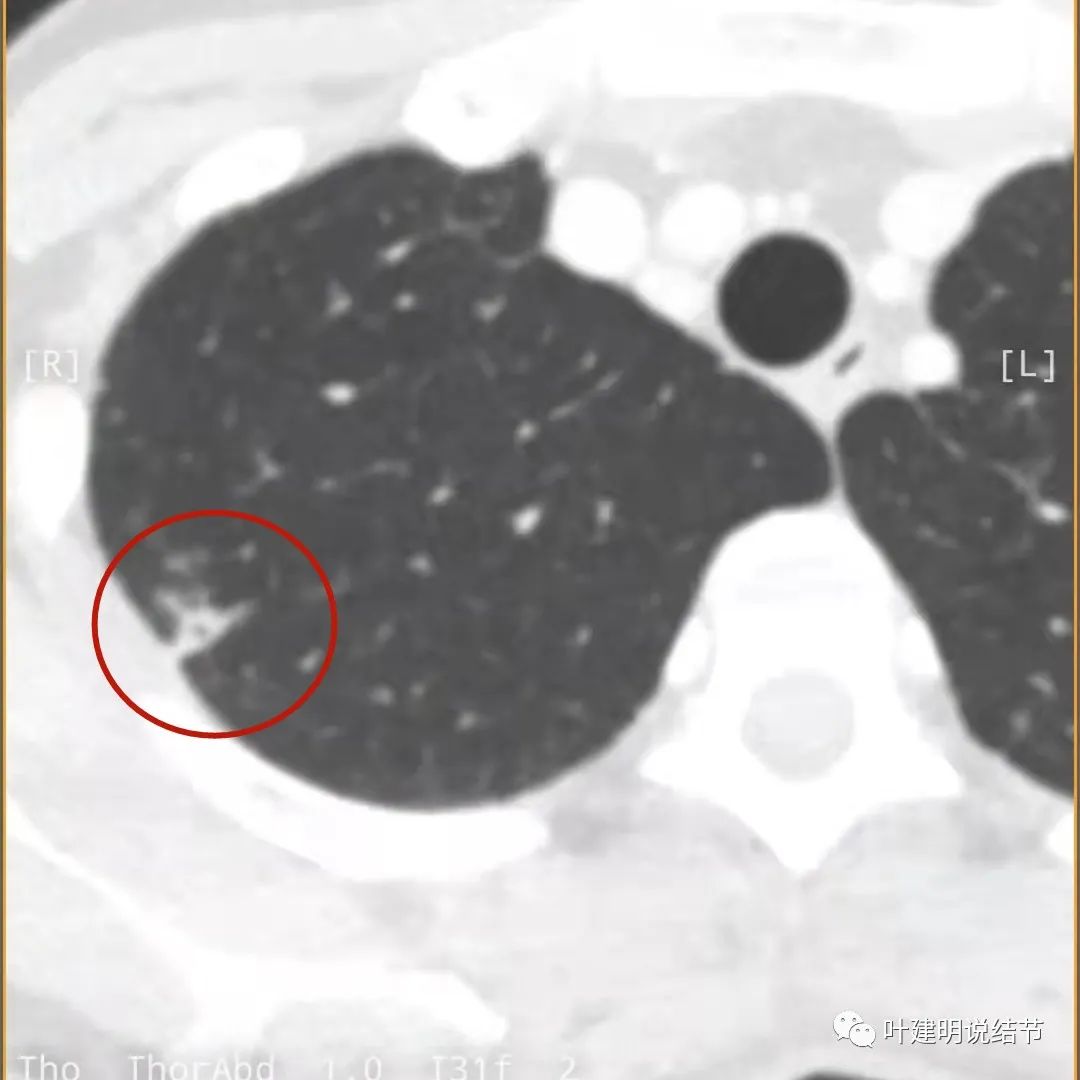

下面是今年复查的平扫片子,来看看有什么变化:

病灶邻近胸膜异常增厚(蓝色箭头)

有卫星灶(绿色箭头),邻近胸膜明显增厚,且模糊,边不清

邻近胸膜增厚